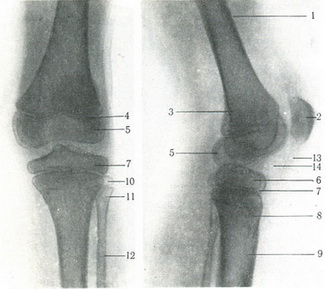

149. Задній (а) і бічний (б) знімки колінного суглоба. 1 - діафіз стегнової кістки; 2 - надколінок; 3 - метафиз; 4 - епіфізарний хрящ стегнової кістки; 6 - епіфіз великогомілкової кістки; 7 - епіфізарний (паростковий) хрящ великогомілкової кістки; 8 - метафиз великогомілкової кістки; 9 - діафіз великогомілкової кістки; 10 - епіфіз малогомілкової кістки; 11 - метафиз малогомілкової кістки; 12 - діафіз малогомілкової кістки; 13 - власна зв'язка наколінка; 14 - «ромбовидное простір» (за рахунок прошарки пухкої сполучної тканини). |